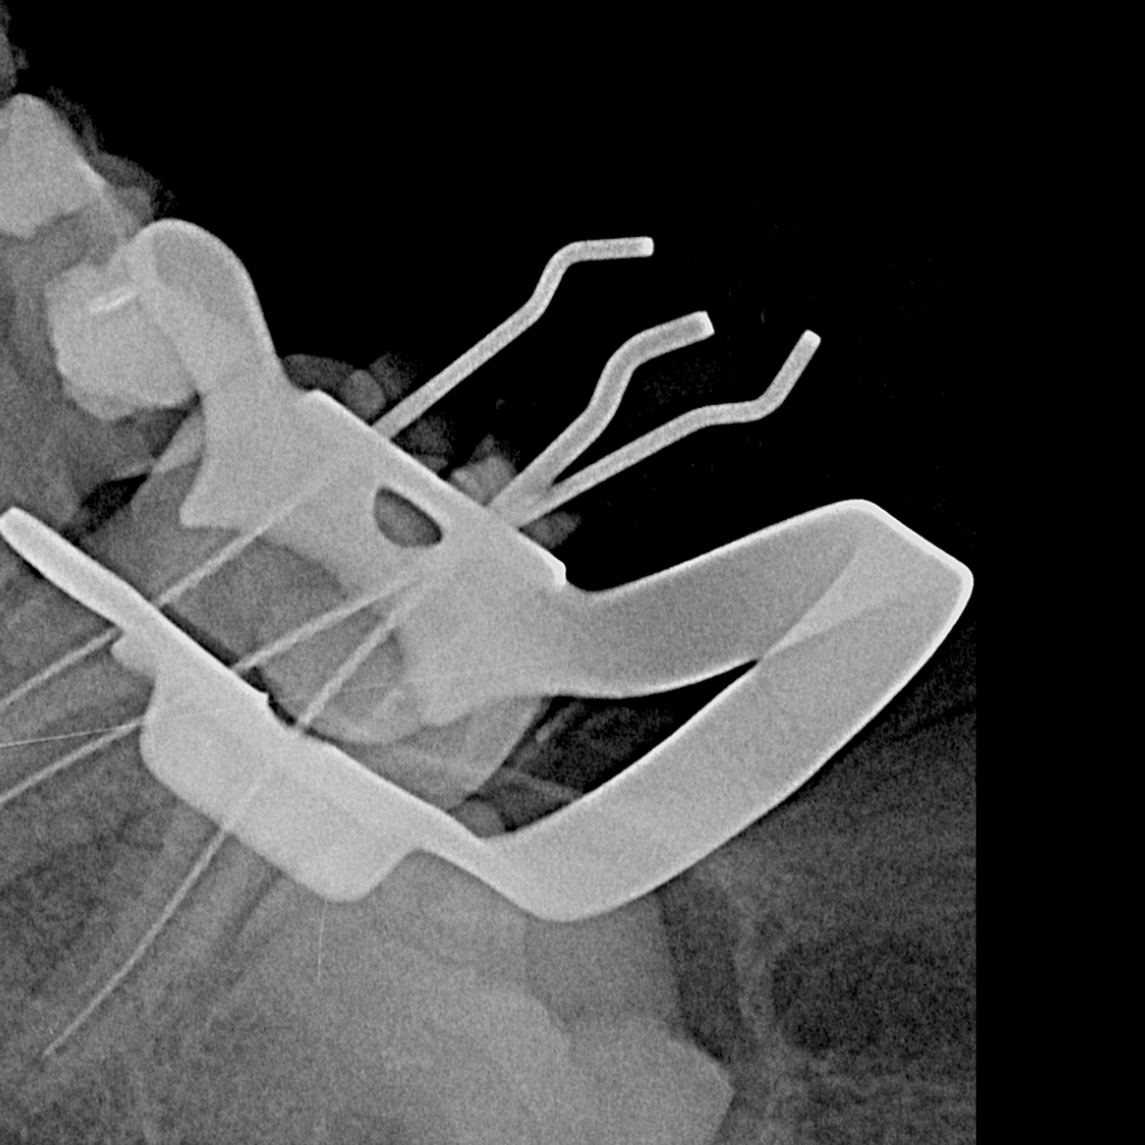

Informarme más aquí.El retratamiento endodóntico es un procedimiento que consiste en volver a tratar un diente que ya...